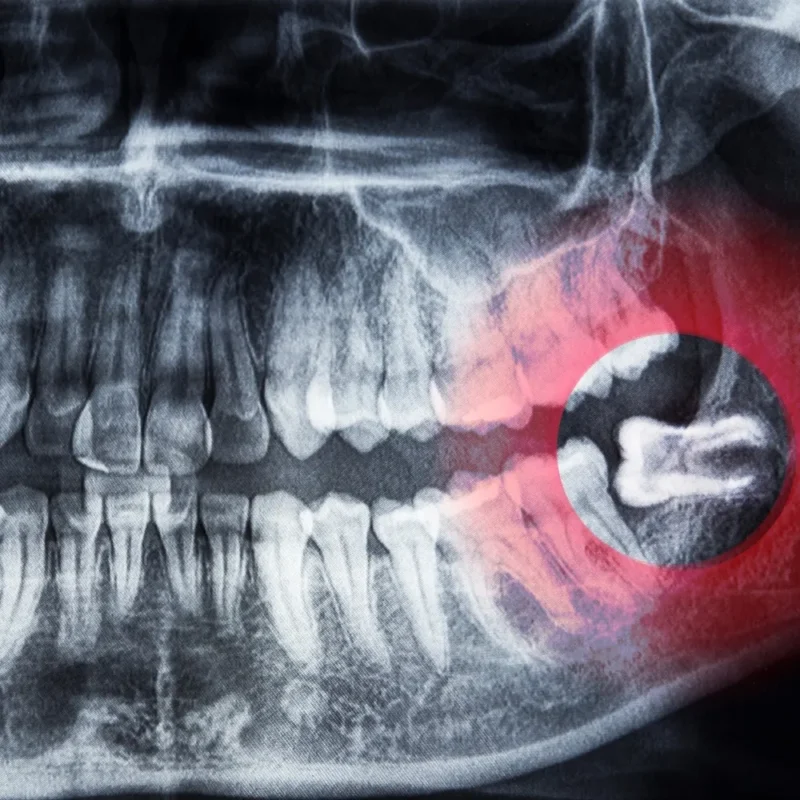

Diyarbakır gömülü 20’lik diş çekimi, hem genç hem de yetişkin bireylerin ağız sağlığı açısından en sık başvurduğu cerrahi işlemlerden biridir. Özellikle çene yapısının dar olduğu durumlarda 20’lik dişlerin düzgün sürememesi, hem ağrıya hem de çevredeki dişlerde baskıya neden olabilir. Gömülü 20’lik diş çekimi zamanında yapılmadığında ciddi diş eti enfeksiyonlarına, çene kemiğinde hasara veya komşu dişlerde […]